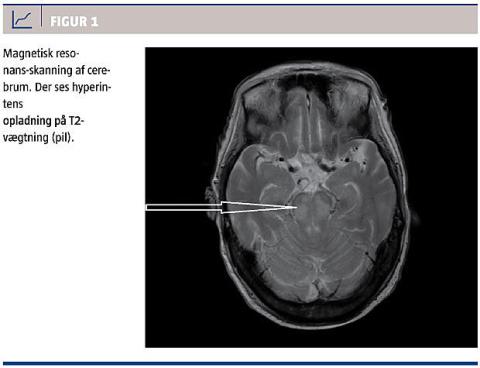

En computertomografi og lumbalpunktur viste normale forhold, og patienten blev efter overflytning til et universitetshospital vurderet af en neurolog, der fandt, at hun havde øjenåbning på stimuli, ingen bevægelser, svage refleksforhold og slap muskeltonus, intakte okulocefale reflekser, cilie- og corneareflekser, lysreaktion samt egenrespiration. De øvrige kranienerver kunne ikke vurderes. Et elektroencefalogram viste 1,5-2 Hz aktivitet i temporalregionerne, mest i venstre side, samt abnorm baggrundsaktivitet 4-6 Hz, ikke reaktivt, hvilket beskrives som et encefalopatisk billede, men ikke kvantitativt nok til at forklare graden af koma. En magnetisk resonans-skanning (Figur 1) på 30. dagen viste, at der var hyperintense signalforandringer på T2 og fluid-attenuated inversion-recovery i capsula externa samt pons, hvilket er foreneligt med ODS. En ny neurologisk vurdering viste, at der var sket en forværring i form af ophævede hjernestammereflekser fraset egenrespiration, og patienten afgik ved døden efter 39 dages indlæggelse.